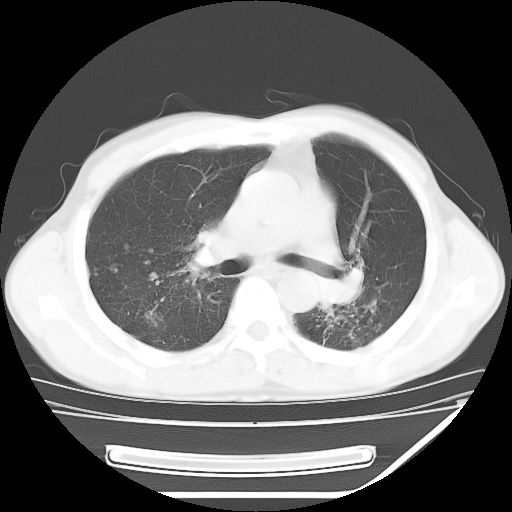

男,59岁,“结核性胸膜炎”30余年,胸部经常疼痛,多次x检查提示“肺部”炎症。腹部疼痛5日,b超提示:“肝内短管结石,余显示不清,建议进一步检查。”

两肺结核并右侧胸腔积液;脾脏、腹腔及腹膜后淋巴结结核[陈旧性];肝内胆管结石

胸部腹部都是结核(双肺。纵隔淋巴结,肝脏,脾脏,肠系膜)